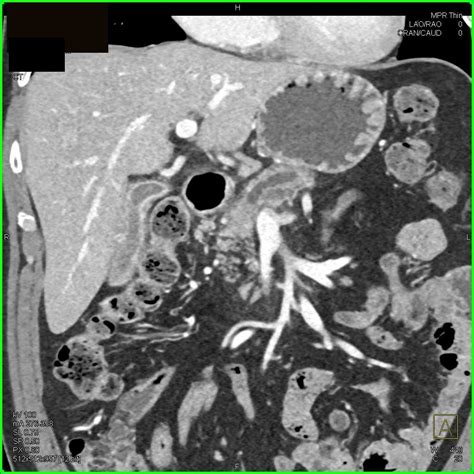

To understand dilation, one must first understand the anatomy. The main pancreatic duct, or the Duct of Wirsung, typically runs the length of the pancreas. In a healthy individual, this duct has a specific, narrow diameter. When a radiologist performs an ultrasound, CT scan, or MRI and notes an enlarged pancreatic duct, they are observing that the diameter of this duct exceeds the normal, expected measurement. This dilation is rarely a condition in itself; rather, it is usually a symptom or a sign of an underlying issue causing back-pressure or blockage within the ductal system.

CT Scan with Contrast Provides detailed cross-sectional images to look for masses, inflammation, or large stones.